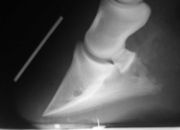

La fourbure est une congestion inflammatoire aiguë du pied. À cause de l'inextensibilité relative de la boîte cornée, elle entraîne un arrêt circulatoire situé avec ischémie des tissus, surtout du tissu kéraphylleux. Il se produit une désunion entre les structures osseuses et cornées, provoquant le basculement de la troisième phalange vers l'avant, caractéristique de cette affection. À l'extrême, la troisième phalange peut perforer la sole. Il s'agit là d'un cas gravissime.

La cause peut être métabolique par excès de nourriture, déshydratation, infections généralisée provoquant la libération d'endotoxines ou rétention placentaire, traumatique, par excès de travail ou surcharge chronique, c'est-à-dire par excès de poids, ou iatrogène par administration de trop grande quantité de corticoïdes. Une fourbure chronique peut se manifester suite à une fourbure aiguë[16].

Le traitement est celui de la cause avec, qui plus est , mise au repos, anti-inflammatoires avec ferrure orthopédique s'il est envisageable de mettre en place un fer en tronquant la pince et en privilégiant l'appui sur les talons. Une plaque et du silicone peuvent être aussi mises en place. Dans les suivis envisageables, citons aussi l'administration d'acépromazine, le patch de nitroglycérine ou la cryothérapie pour la vasodilatation, la mise en place d'une litière épaisse au box, ou encore la saignée dans les 12 heures après les premiers symptômes en cas de surcharge alimentaire[16]. Des inhibiteurs du TNF sont quelquefois utilisés[17].

Le diagnostic repose sur l'examen de la locomotion (appui préférentiel sur la pince), examen à la pince à sonder (réveillant une douleur à la pression en travers des talons) et les radiographies (essentiellement, aspect de géodes ou d'amincissement du naviculaire). Le diagnostic de certitude est cependant quelquefois complexe à apporter.